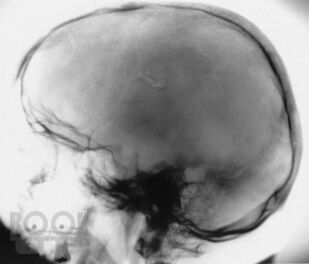

Учебное пособие написано в соответствии с основной профессиональной образовательной программой — программой подготовки кадров высшей квалификации в ординатуре по специальности 31.08.56 «Нейрохирургия». Издание содержит 144 ситуационные задачи. В задачах приводятся клинические случаи по всем разделам программы, в том числе рассматриваемые на смежных с нейрохирургией дисциплинах. Особое внимание уделено клиническим примерам, иллюстрирующим основные неотложные состояния у пациентов и раненых нейрохирургического профиля.

Ситуационные задачи составлены с целью обучения ординаторов методике диагностики травм и заболеваний нервной системы; также они могут быть актуальными и для практикующих нейрохирургов в качестве справочного пособия, в котором приведены алгоритмы диагностики и стандарты оказания помощи при наиболее распространенных нейрохирургических заболеваниях и травмах.